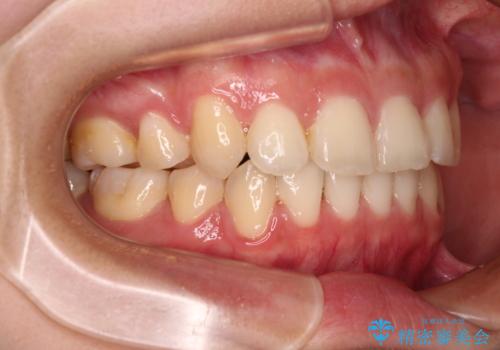

骨格的に下顎が左側に変位していたため、上下正中を合わせることは困難であることは分かっていましたが、可能な限り合わせることができました。

骨格的なズレがあると仕上げの段階で奥歯の咬み合わせが不安定となるため、予定よりやや長期間となりました。